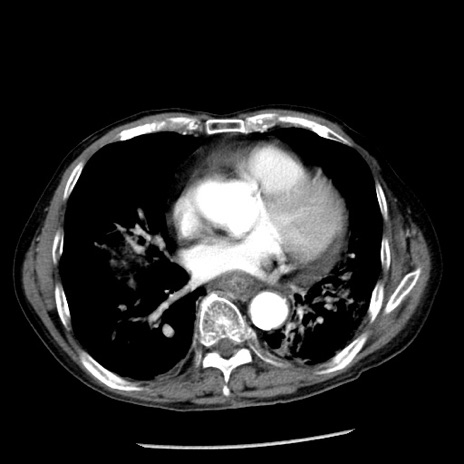

症例26(横断像)

【症例】80歳代男性

【主訴】嘔吐

【現病歴】昨晩2回嘔吐あり、今朝になっても嘔吐あり。来院。

【既往歴】胃潰瘍

【身体所見】意識清明、BT 37.6℃、BP 166/95mmHg、HR 100bpm、SpO2 97%、腹部:平坦・軟、腸蠕動音聴取良好、圧痛なし。

【データ】WBC 21900、CRP 1.46